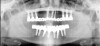

There are several ways to diagnose periodontitis. In addition to soft tissue evaluation, one of the most common and accurate methods is to use a periodontal probe in affected areas and record probing depths. Bleeding on probing is another indication of unhealthy periondontal tissues. Radiographs can be used, but they have limitations in initial diagnosis because bone loss is typically associated with severe and chronic periodontal disease; therefore, radiographs are better used to confirm diagnosis. However, vertical bitewings taken over time can be placed side-by-side to detect even slight differences in contrast.